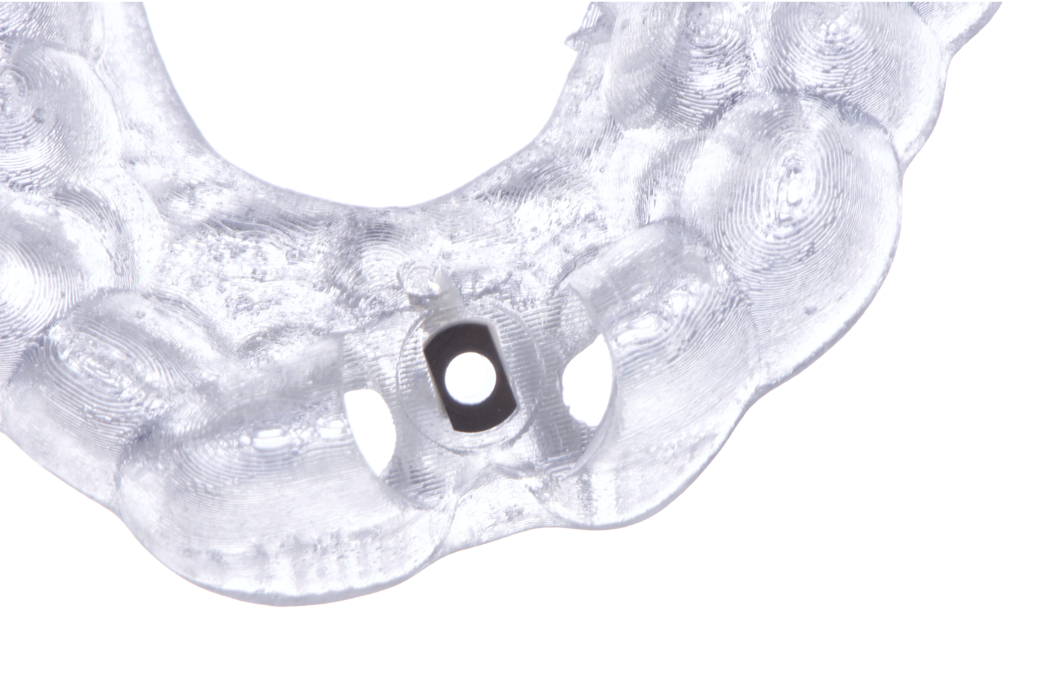

The surgical protocol began with the atraumatic extraction of tooth 1.1 to preserve as much of the alveolar socket as possible. Immediately following extraction, an N1 implant was placed into the socket using a guided surgical approach to ensure ideal three-dimensional positioning. The “one abutment one time” technique was applied to minimize soft tissue manipulation during the healing phase, which is particularly important in esthetic areas.